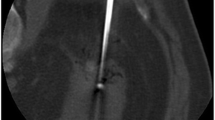

Percutaneous renal cryoablation procedure

A Siemens SOMATOM Definition AS CT system was used in the scanner suite alongside a BTG system (BTG, London, UK) for cryoablation. The procedure was performed by one of four radiologists with between 1 and 10 years of dedicated ablation experience. During the procedure, patients were in general anesthesia, and in a prone-oblique position.

For planning and target facilitation, a contrast-enhanced triple-phase CT scan of the kidneys was conducted. If needed, an intraprocedural coaxial biopsy of the tumor was performed using an 18-gauge semiautomatic needle prior to cryoprobe placement. Real-time CT fluoroscopy was used to guide needle placement. The number and type of cryoprobes were determined by the attending radiologist. If necessary, hydrodissection with sterile saline was carried out to displace thermally sensitive structures. At the discretion of the attending radiologist, truncated helical acquisitions covering the RM were acquired during placement of cryoprobes to confirm their position. In all cases truncated helical acquisitions for monitoring of the size and location of the ice ball were performed during two treatment cycles of freeze–thaw treatment (in general 10 min freeze, 8 min thaw, 10 min freeze) at 4-min intervals for a total of four acquisitions to confirm extension of the ice ball at least 5 mm beyond the tumor margin. The duration of each cycle and the power of each probe could be adjusted as to prevent adjacent vulnerable organ injury or inadequate ice ball coverage. Fluoroscopy was conducted as sequential scans at 5.0 mm slice thickness with 120 kV and a starting point of 40 mAs, which could be increased according to patient size. Images for the triple-phase CT were obtained as helical acquisitions at 2.0 mm slice thickness using standard CT technique (120 kV peak and approximately 200 mAs) with dose modulation using automatic exposure control. The same parameters were used in addition to a current of 150 mAs for the truncated CT acquisitions.